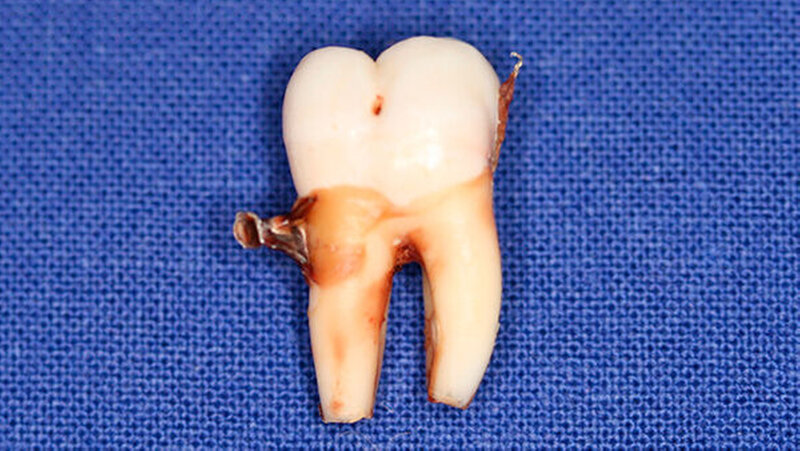

Postoperativ wurden die Zähne in bukko-lingualer Richtung mittels einer diamantbelegten Trennscheibe geteilt. Visuell zeigte sich nun ein großer Hohlraum im koronalen Dentinbereich, sowohl an Zahn 27 als auch an Zahn 47. Die histologische Untersuchung der Zahnfragmente ergab für beide Zähne: Zahnanlagengewebe mit akuter Entzündung (Abbildungen 4 bis 6). Der Patient befindet sich seitdem im regelmäßigen Abstand von sechs Monaten in einem prophylaktischen Recall. Die Abbildung 7 zeigt das postoperative Zahnschema vom 19. August 2015

Der vorliegende Fall zeigt eindrucksvoll verschiedene Stadien der präeruptiven koronalen Resorption (PIR): eine präeruptiv im Röntgenbild sichtbare Transluzenzzone im Dentin des Zahns 47 an der koronalen Schmelz-Dentin Grenze mit intaktem Schmelzmantel und eine große Kavitätenbildung nach Durchbruch des Zahns 27 in die Mundhöhle.

Bei der histologischen Untersuchung der extrahierten Zähne 27 und 47 unseres Patienten wurden Zahnanlagengewebe und Entzündungszellen gefunden. Im Rahmen anderer Untersuchungen konnten resorptive Zellen wie Osteoklasten und Makrophagen an den Rändern der Läsion nachgewiesen werden [Spierer, 2014].